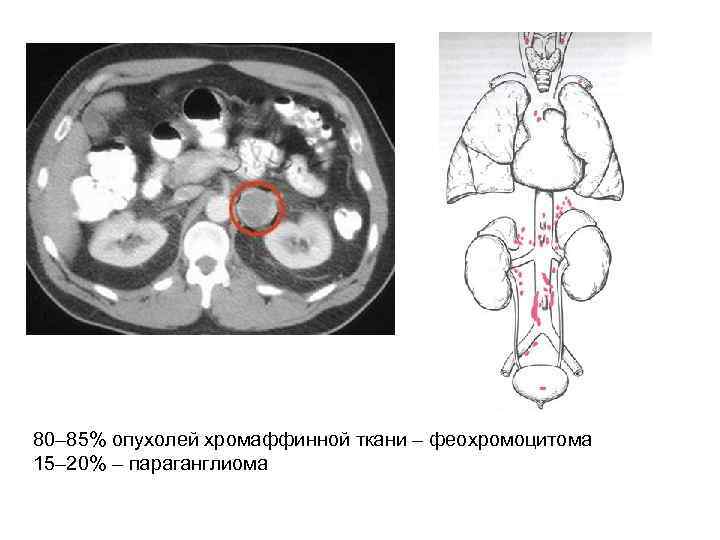

Феохромоцитома (ФХЦ) • Феохромоцитома – это опухоль мозгового слоя надпочечника, состоящая из хромаффинных клеток, продуцирующая катехоламины (адреналин, норадреналин и дофамин). • Параганглиома – это опухоль, состоящая из вненадпочечниковой хромаффинной ткани симпатических паравертебральных ганглиев грудной клетки, брюшной полости и таза.

80– 85% опухолей хромаффинной ткани – феохромоцитома 15– 20% – параганглиома